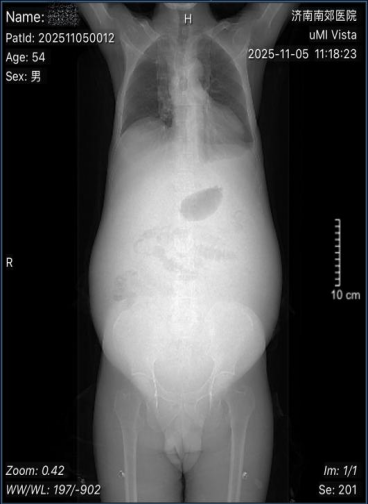

赵先生(化名)因长期饮酒40余年出现纳差、乏力、上腹隐痛、呕血,曾就诊多家医院诊断为“酒精性肝硬化、食管静脉曲张”。近一月,病情急剧恶化:腹胀如鼓、全腹胀痛,排便困难,双下肢水肿,更出现胸闷、夜间无法平卧的严重压迫症状,口服多种药物及中药未见好转。为求生机,赵先生慕名来到济南南郊医院消化科任淑红主任的专家门诊,以“肝硬化腹水”收治入院。

入院时,赵先生腹围高达100.5厘米,体重仅62公斤,大量腹水引发的严重压迫症状已危及生命,常规药物治疗收效甚微。济南南郊医院消化内科团队迅速响应,根据《2025版肝硬化临床诊治管理指南》制定了周密的综合治疗方案及后续如果出现食管-胃底静脉曲张破裂出血即将进行的套扎及硬化止血替代方案:

经半月治疗,赵先生现在活动自如,健步如飞,夜间能平稳休息,腹围从100.5厘米显著缩减至85厘米,整体状况明显改善。针对赵先生情况,为减少腹水生长速度、消化道再出血、肝性脑病、肝肾综合征的发生,南郊医院消化科医疗团队为其设定长期慢病管理的精准吃、喝、动、查方案。